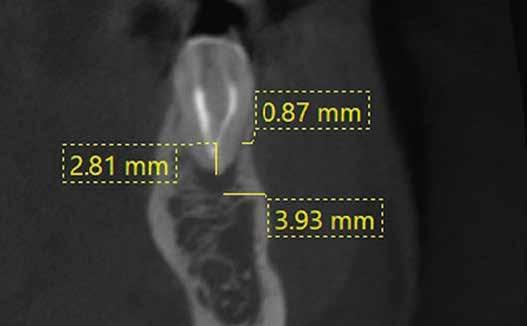

1. a–f ábrák: A cingulumon keresztül gömbfúróval kialakított hozzáférés a trepanációs kavitás labiális irányba történő túlzott mértékű kiterjesztését eredményezheti, és ez lényegesen növelheti a perforáció esélyét (a). A guttapercha átsejlik a lágyrészek alatt (b). Klinikailag igazolt perforáció (c). A preoperatív sagittális irányú CBCT-szeleten jól látható a labiális perforáció (d). Labiális irányú perforáció (fekete nyíl; e). A tényleges gyökércsatorna (piros nyíl; f).

5. a–l. ábrák: Az incisális élen keresztül kialakított hozzáférés lehetővé teszi a pericervikális dentin megőrzését. Kalcifikáció esetén CBCT-felvétel készítése hasznosnak bizonyulhat a hozzáférési nyílás tervezése során (a–d) . Minden fog koronai helyreállítása a gyökértömés elkészítésével egyidejűleg történt. A négyéves (e–h) és a kétéves (i–l) kontrollok alkalmával készített röntgenfelvételeken teljes gyógyulás látható. Mindkét fog tünetmentes és funkcióképes volt. (Dr. Viraj Vora esetei)

zésére. Ez azért fontos, mert a frontfogak funkcionális megterhelése során – a PCD-nek megfelelően elhelyezkedő területben – jelentős stressz ébred (5. a–l ábrák) 24 Szükség esetén egy CBCT-felvételt is készíthetünk. A 3D-s adatok jelentős mértékben segíthetik a klinikus munkáját a gyökércsatorna koronális vetületének vizualizálásában, és ennek alapján az egyenes vonalú hozzáférés biztosításához szükséges belépési pont meghatározásában (5.